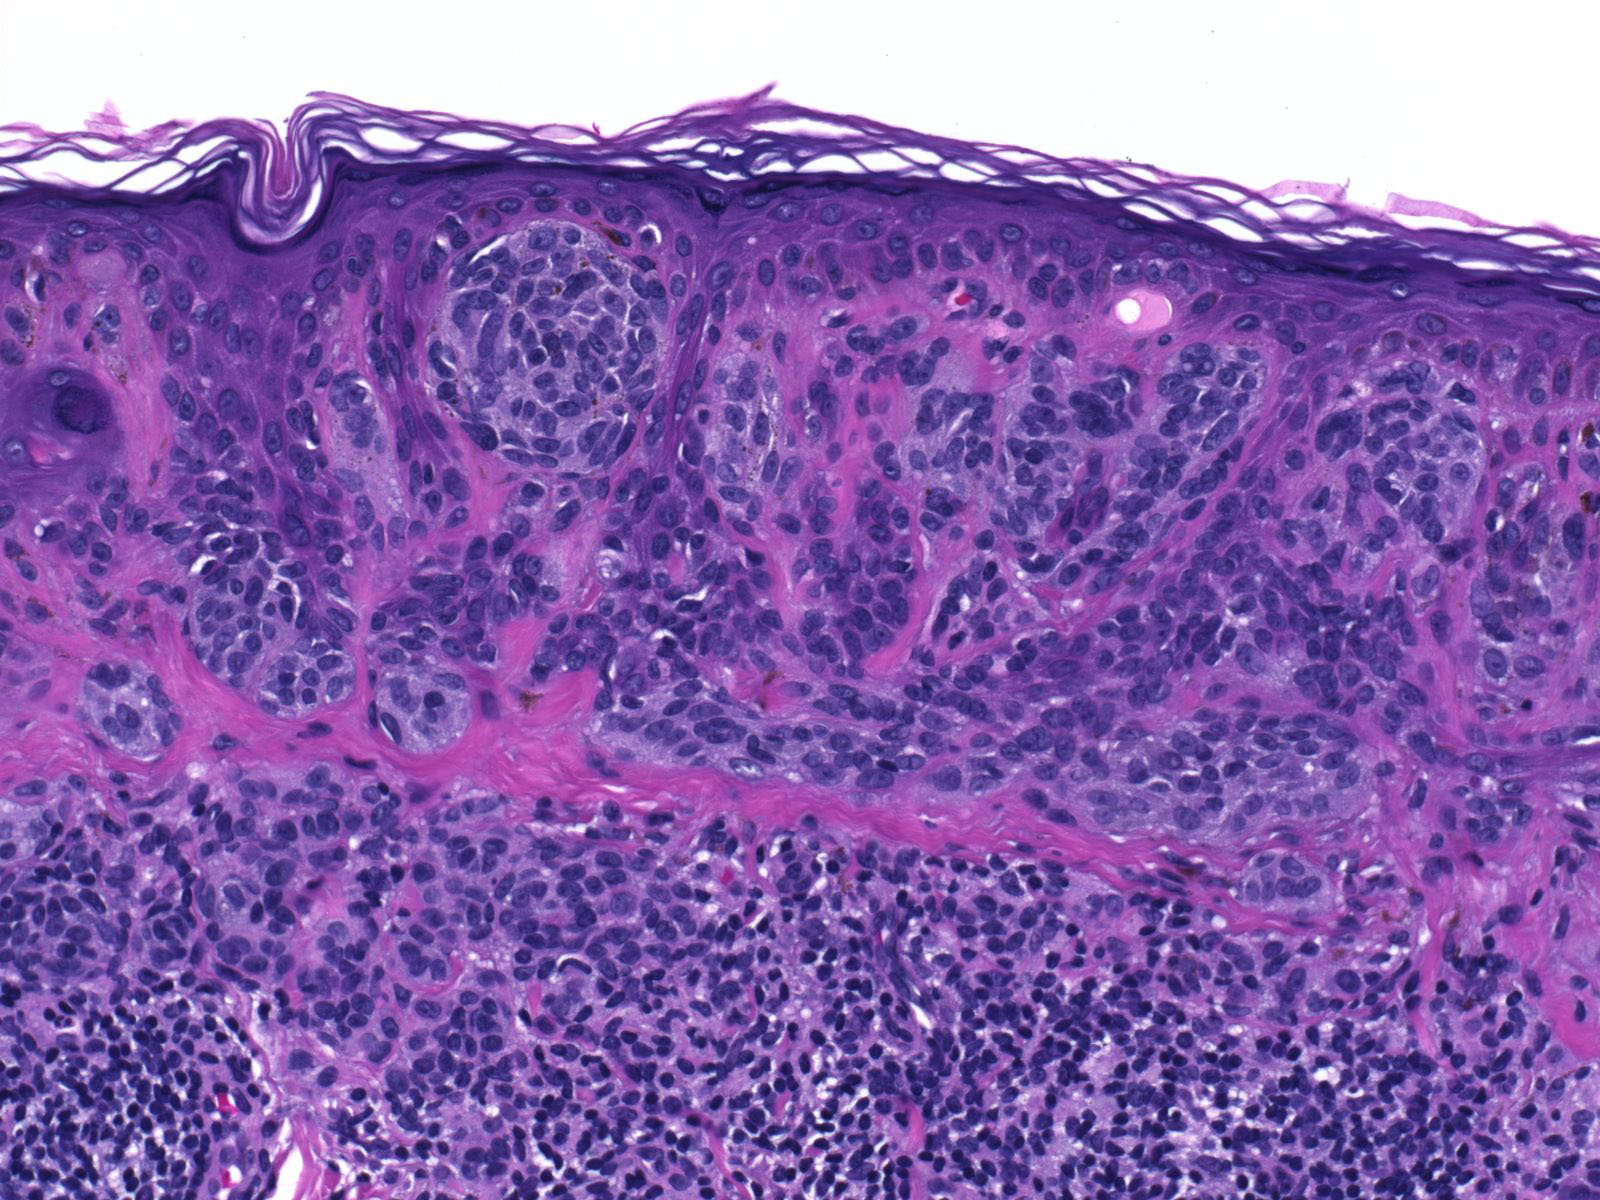

Autotrapianto di cellule per curare la vitiligine, malattia cronica della pelle caratterizzata da macchie bianche che si formano per la carenza o la totale mancanza delle cellule responsabili della pigmentazione cutanea, dette melanociti. E’ l’ultima delle soluzioni, presentata oggi all’Istituto Dermatologico San Gallicano (ISG) in occasione di un convegno sulla malattia che colpisce uomini e donne senza differenza di genere con un’incidenza pari allo 0,5-2% della popolazione mondiale. 80 milioni sono le persone affette da vitiligine di cui oltre un milione solo in Italia e la familiarita’ si riscontra fino al 30% dei casi. La vitiligine puo’ iniziare a qualsiasi eta’ ma nel 50% dei casi si manifesta tra i 10 e i 30 anni.

Le persone affette tendono spesso all’isolamento a causa dei disagi sociali e di relazione che possono sperimentare. La tecnica di trapianto autologo di melanociti prevede il prelievo di un piccolo frammento superficiale di cute dal cuoio capelluto. Le cellule vengono trattate e poi autotrapiantate nel paziente Dopo circa 10 giorni, si procede alla stimolazione delle cellule impiantate e dei melanociti con il laser ad eccimeri, per arrivare alla ripigmentazione completa della zona nell’arco di circa tre mesi. L’Istituto Dermatologico San Gallicano, il primo centro in Italia ad utilizzare 10 anni fa la fototerapia UVB a banda stretta, ”gold standard” nella cura della patologia, ora introduce un nuovo metodo terapeutico sviluppato a Bordeaux dal Prof. Yvon Gauthier: appunto, il trapianto autologo dei melanociti. L’Istituto San Gallicano, ha spiegato il Professor Francesco Bevere, Direttore Generale dell’ISG e dell’Istituto Regina Elena, sta vivendo una crescita esponenziale di attivita’ cliniche e di ricerca e si prepara ad affrontare nuovi obiettivi grazie anche all’acquisizione di tecnologie innovative utili a proseguire e ad incentivare i traguardi clinico scientifici gia’ raggiunti. Bevere ha appena formalizzato l’adesione dell’ Istituto San Gallicano al consorzio regionale per la realizzazione del centro polifunzionale di medicina rigenerativa, proprio finalizzato alla rigenerazione tissutale. La prossima sfida sara’ quindi la banca della pelle. Il San Gallicano e’ impegnato in un progetto internazionale di screening dei geni potenzialmente responsabili della vitiligine, ha spiegato il professor Mauro Picardo: si tratta di uno studio coordinato dal prof. Spritz dell’Universita’ del Colorado (USA) e che vede la partecipazione di molti dei maggiori centri americani, europei e asiatici di ricerca clinica e sperimentale sulla vitiligine. (ANSA).